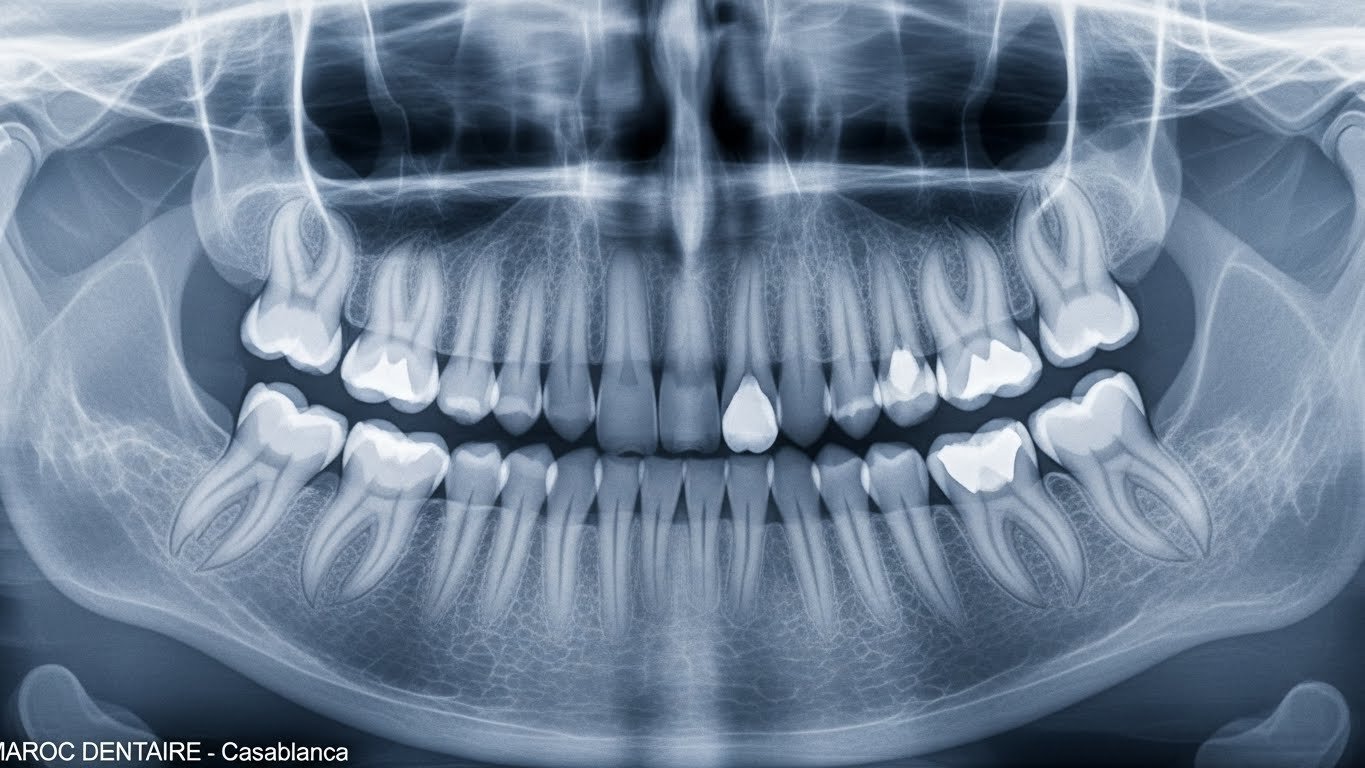

La radiographie rétro-alvéolaire est une radio dentaire de petite taille qui permet d’examiner en détail une zone précise de votre bouche, généralement 1 à 3 dents. Contrairement à la radiographie panoramique qui montre toute votre mâchoire, la rétro-alvéolaire offre une image très précise d’une zone ciblée.

En Quoi Est-elle Différente des Autres Radios Dentaires ?

Pour bien comprendre quand utiliser quelle radio, voici un tableau comparatif des trois principales techniques d’imagerie dentaire disponibles au Maroc :

| Type d’examen | Zone couverte | Précision | Prix au Maroc | Usage principal |

|---|---|---|---|---|

| Radiographie rétro-alvéolaire | 1-3 dents | Très haute | 100 DH | Diagnostic ciblé, caries entre dents, contrôle de traitement |

| Radiographie panoramique | Toutes les dents + mâchoires | Moyenne | 200 DH | Bilan général, orthodontie, dents de sagesse |

| Cone Beam (Scanner 3D) | Zone sélectionnée en 3D | Maximale | 1200 DH | Implants, chirurgie complexe, analyse 3D |